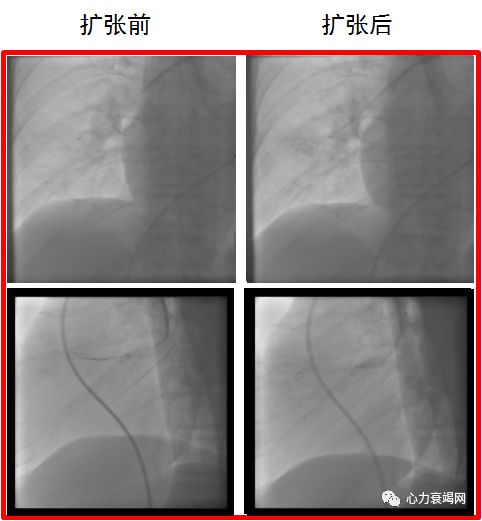

2017-04-25左下肺动脉A8完全闭塞开通

2017-06-27右肺动脉A5血管扩张术前后对比

2017-09-14右肺动脉A6完全闭塞开通

球囊扩张术后肺动脉压力由120/48(72)mmHg降至90/32(51)mmHg